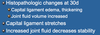

List the Factors playing a Role in Pathogenesis of Chronic Cranial Cruciate Ligament Disease

Degeneration of Cranial Cruciate Ligament Occurs with Age- This Degeneration tends to be worse in Larger Dogs (Over 15 kg/ 30lbs)

Factors that Contribute to Degeneration:

Obesity/Poor Fitness- More Stress/Strain on Ligaments

Conformation- Conformation of Femur, or even Stance/Gait would place Additional Stress on the Ligament

Excessive Plateau Angle- If the Slope is Steeper, the CCL would be under Greater Strain